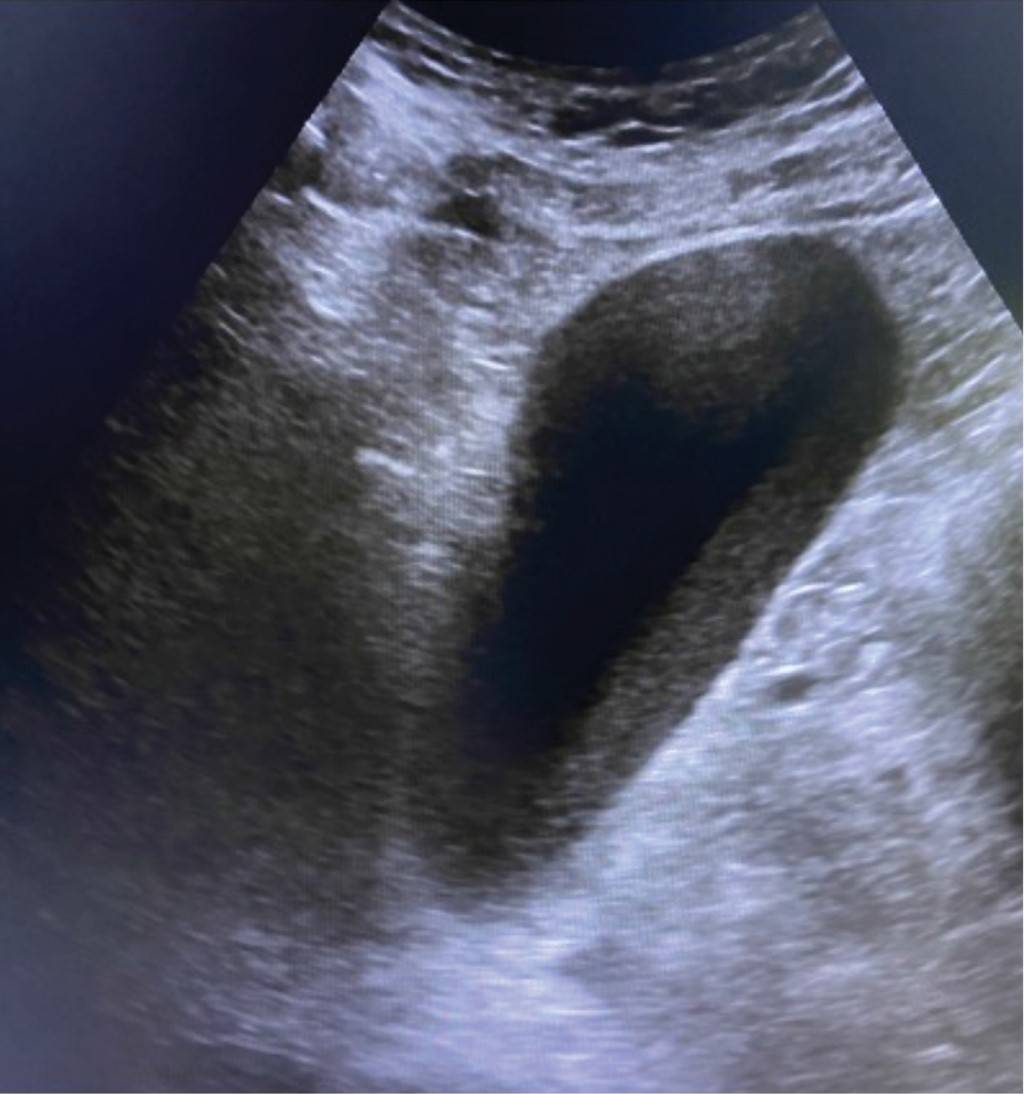

Ante la falta de diagnóstico preciso, se realizó tomografía de abdomen en donde no se pudo documentar alguna patología intraabdominal que justificara el dolor del paciente y que reportó nuevamente la presencia de lodo biliar, pero ninguna alteración vesicular o biliar agregada (Figura 2). Después de unas horas de observación sin analgésicos, el dolor volvió a incrementarse y fue más evidente su localización en el hipocondrio derecho. Un segundo ultrasonido, realizado por otro radiólogo, interpretó incremento generalizado de las dimensiones de la vesícula con franco engrosamiento parietal de 8 mm, escasa cantidad de líquido perivesicular, imagen en "tela de cebolla", signo de Murphy sonográfico positivo y ecos que ocupaban el cuello vesicular y proyectaban sombra acústica posterior (Figura 3). El paciente fue sometido a colecistectomía laparoscópica, donde se encontró vesícula severamente inflamada, con engrosamiento generalizado de su pared, gran distensión y datos de isquemia focal (Figura 4).

Figura 3